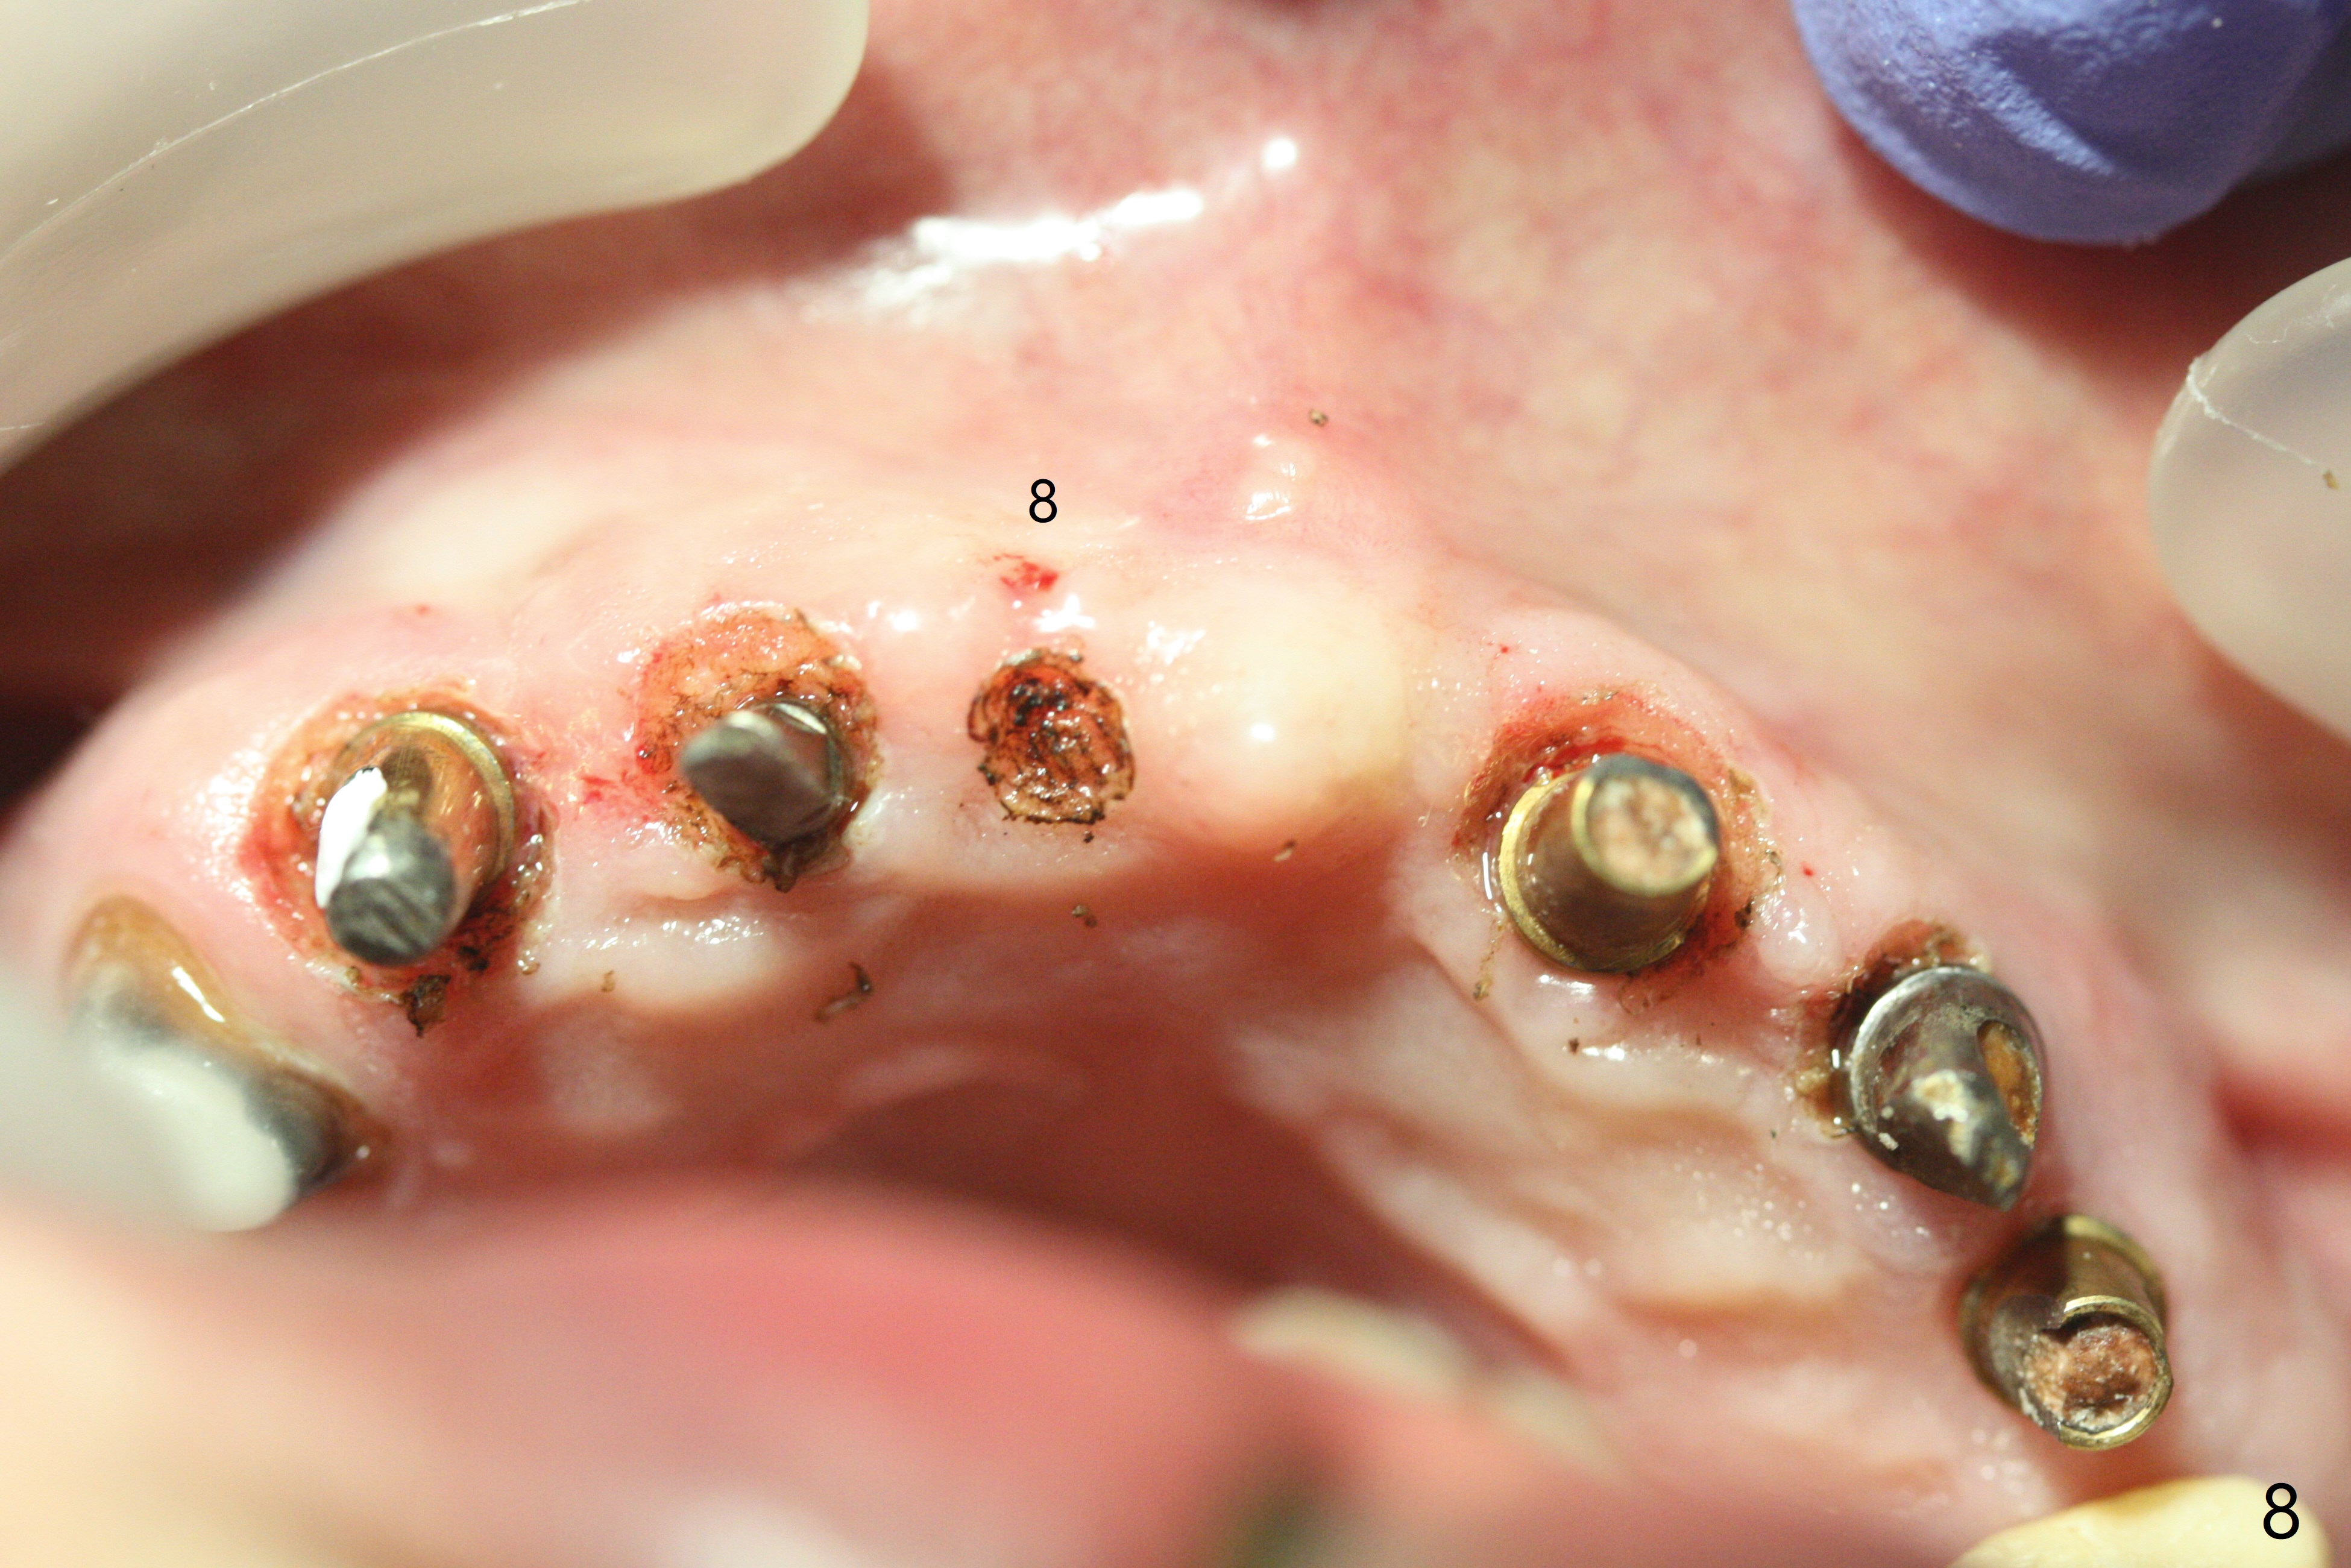

With temporarization of #3,4,13-15 (Fig.1), the anterior clearance is maintained (Fig.2). When provisional is removed, there is no papilla between #7 and 8 (Fig.3,4). After confirmation of complete seating of the abutments at #6 and 10 (Fig.5,6), gingivectomy is conducted with Diode laser (Fig.7,8). Following provisional being relined and modified, the anterior papillae form (Fig.9).